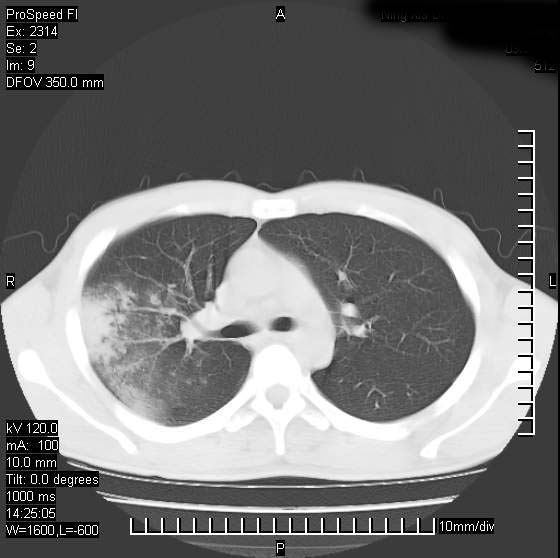

男性,再生障碍性贫血,入院前发热10天,最高40c,右侧胸痛,外院ct示右上,中肺边缘模糊的球性影(就是我现在图中标示的范围),考虑炎症,在我院使用头孢呋辛,洛美沙星10天,高烧消退,自感下午稍有发热,但今天ct示右上,中肺病灶明显扩大,还是考虑炎症,看其中的球型影是否霉菌感染??,是否能排除结核?

肺脓肿,伴双肺播散

片状高密度影内见空洞影,内可见球形软组织密度影,并有新月征,考虑霉菌感染.

支持右肺上叶、中叶外侧段节段性肺炎伴脓肿形成。